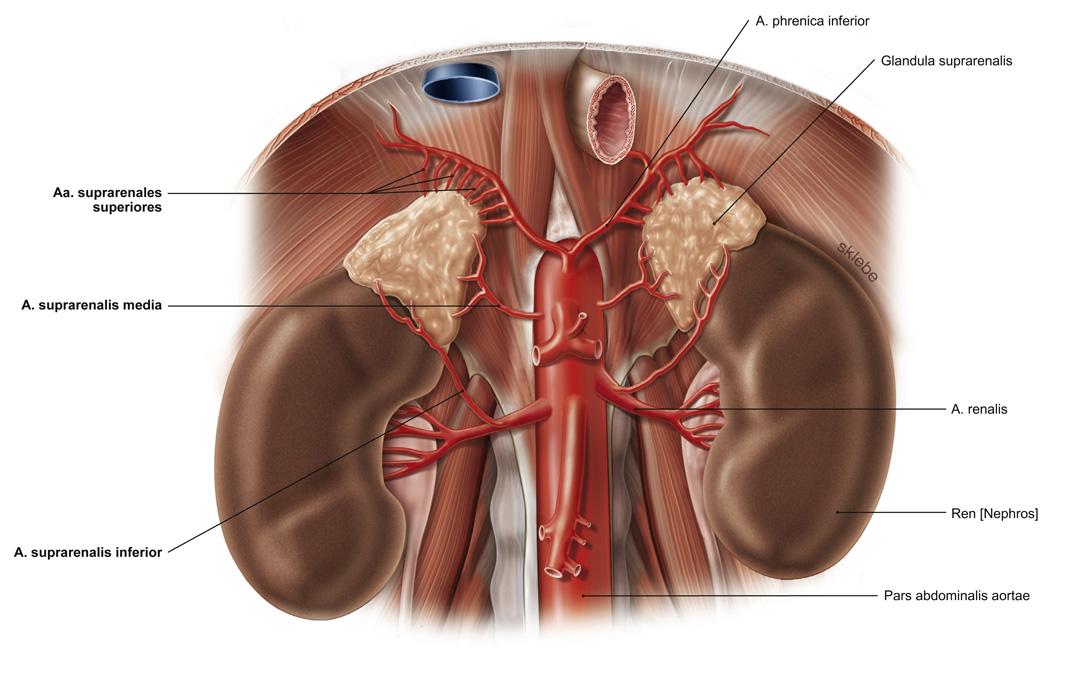

Fig 3.25: Aorta abdominalis - pare viscerale takken

|

|